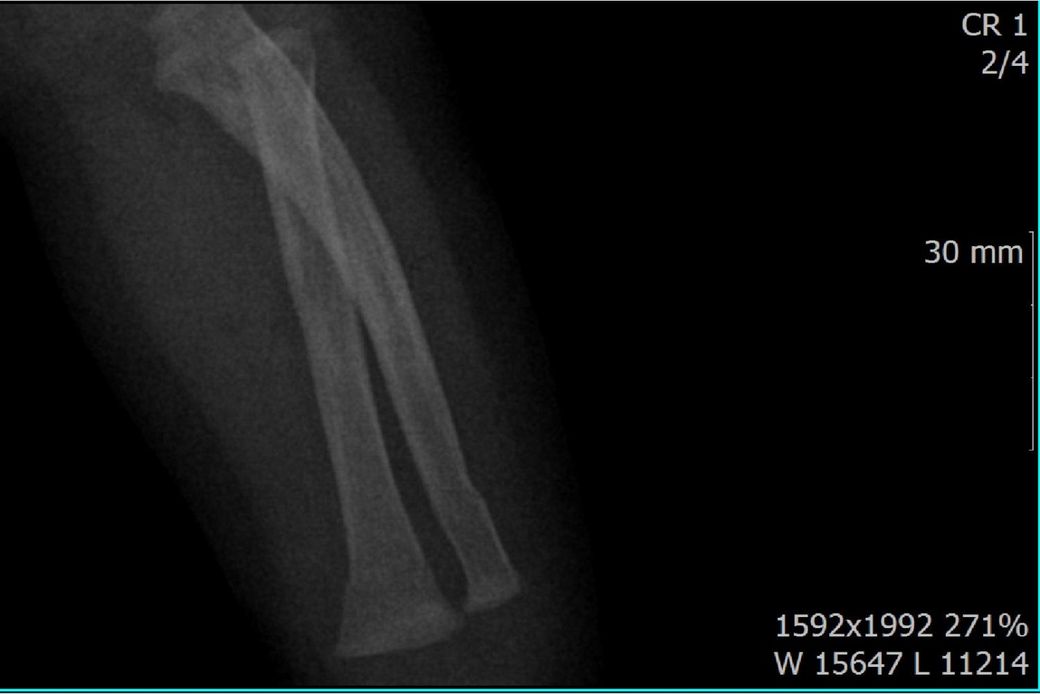

다름이 아니라, 첨부드린 엑스레이(X-ray) 사진처럼 골절 사실을 알게 되고 골절 발생 시점 대략적으로나마 추정시기를 파악하려고 문의 드리게 되었습니다

1) 3월 30일 촬영한 X-ray만으로 정확한 골절 시기를 100% 특정하는 데에는 한계가 있다는 점 충분히 인지하고 있기에 촬영날짜 기준으로 대략적으로 어느정도 시점에서 발생되었을 것으로 추측(ex 당일, 7~10일전, 7~14일 전, 10일 ~ 20일전, 14일 ~ 30일전 등등등)되는지 이해하고 싶습니다.

• 3번 째 사진

하지만, 아예 불가능한건 아니고 골절선이 얼마나 뚜렷하냐, 골막 반응이 보이느냐, 연골성 가골 형성이 있느냐 등으로 골절 시기를 추정해볼 수 있습니다.

골절선이 뚜렷하면 0~1주, 골막 반응이 시작되면 1~2주, 연골성 가골이 형성되기 시작하면 2~3주, 가골이 명확해지면 3~6주 정도로 추정할 수 있습니다.

골절선이 흐려졌고 가골이 형성되기 시작하는 2~3주경이 아닌가 의심이 되지만 제가 골절을 주로 보는 정형외과 전문의가 아니라서 정확도가 떨어집니다.